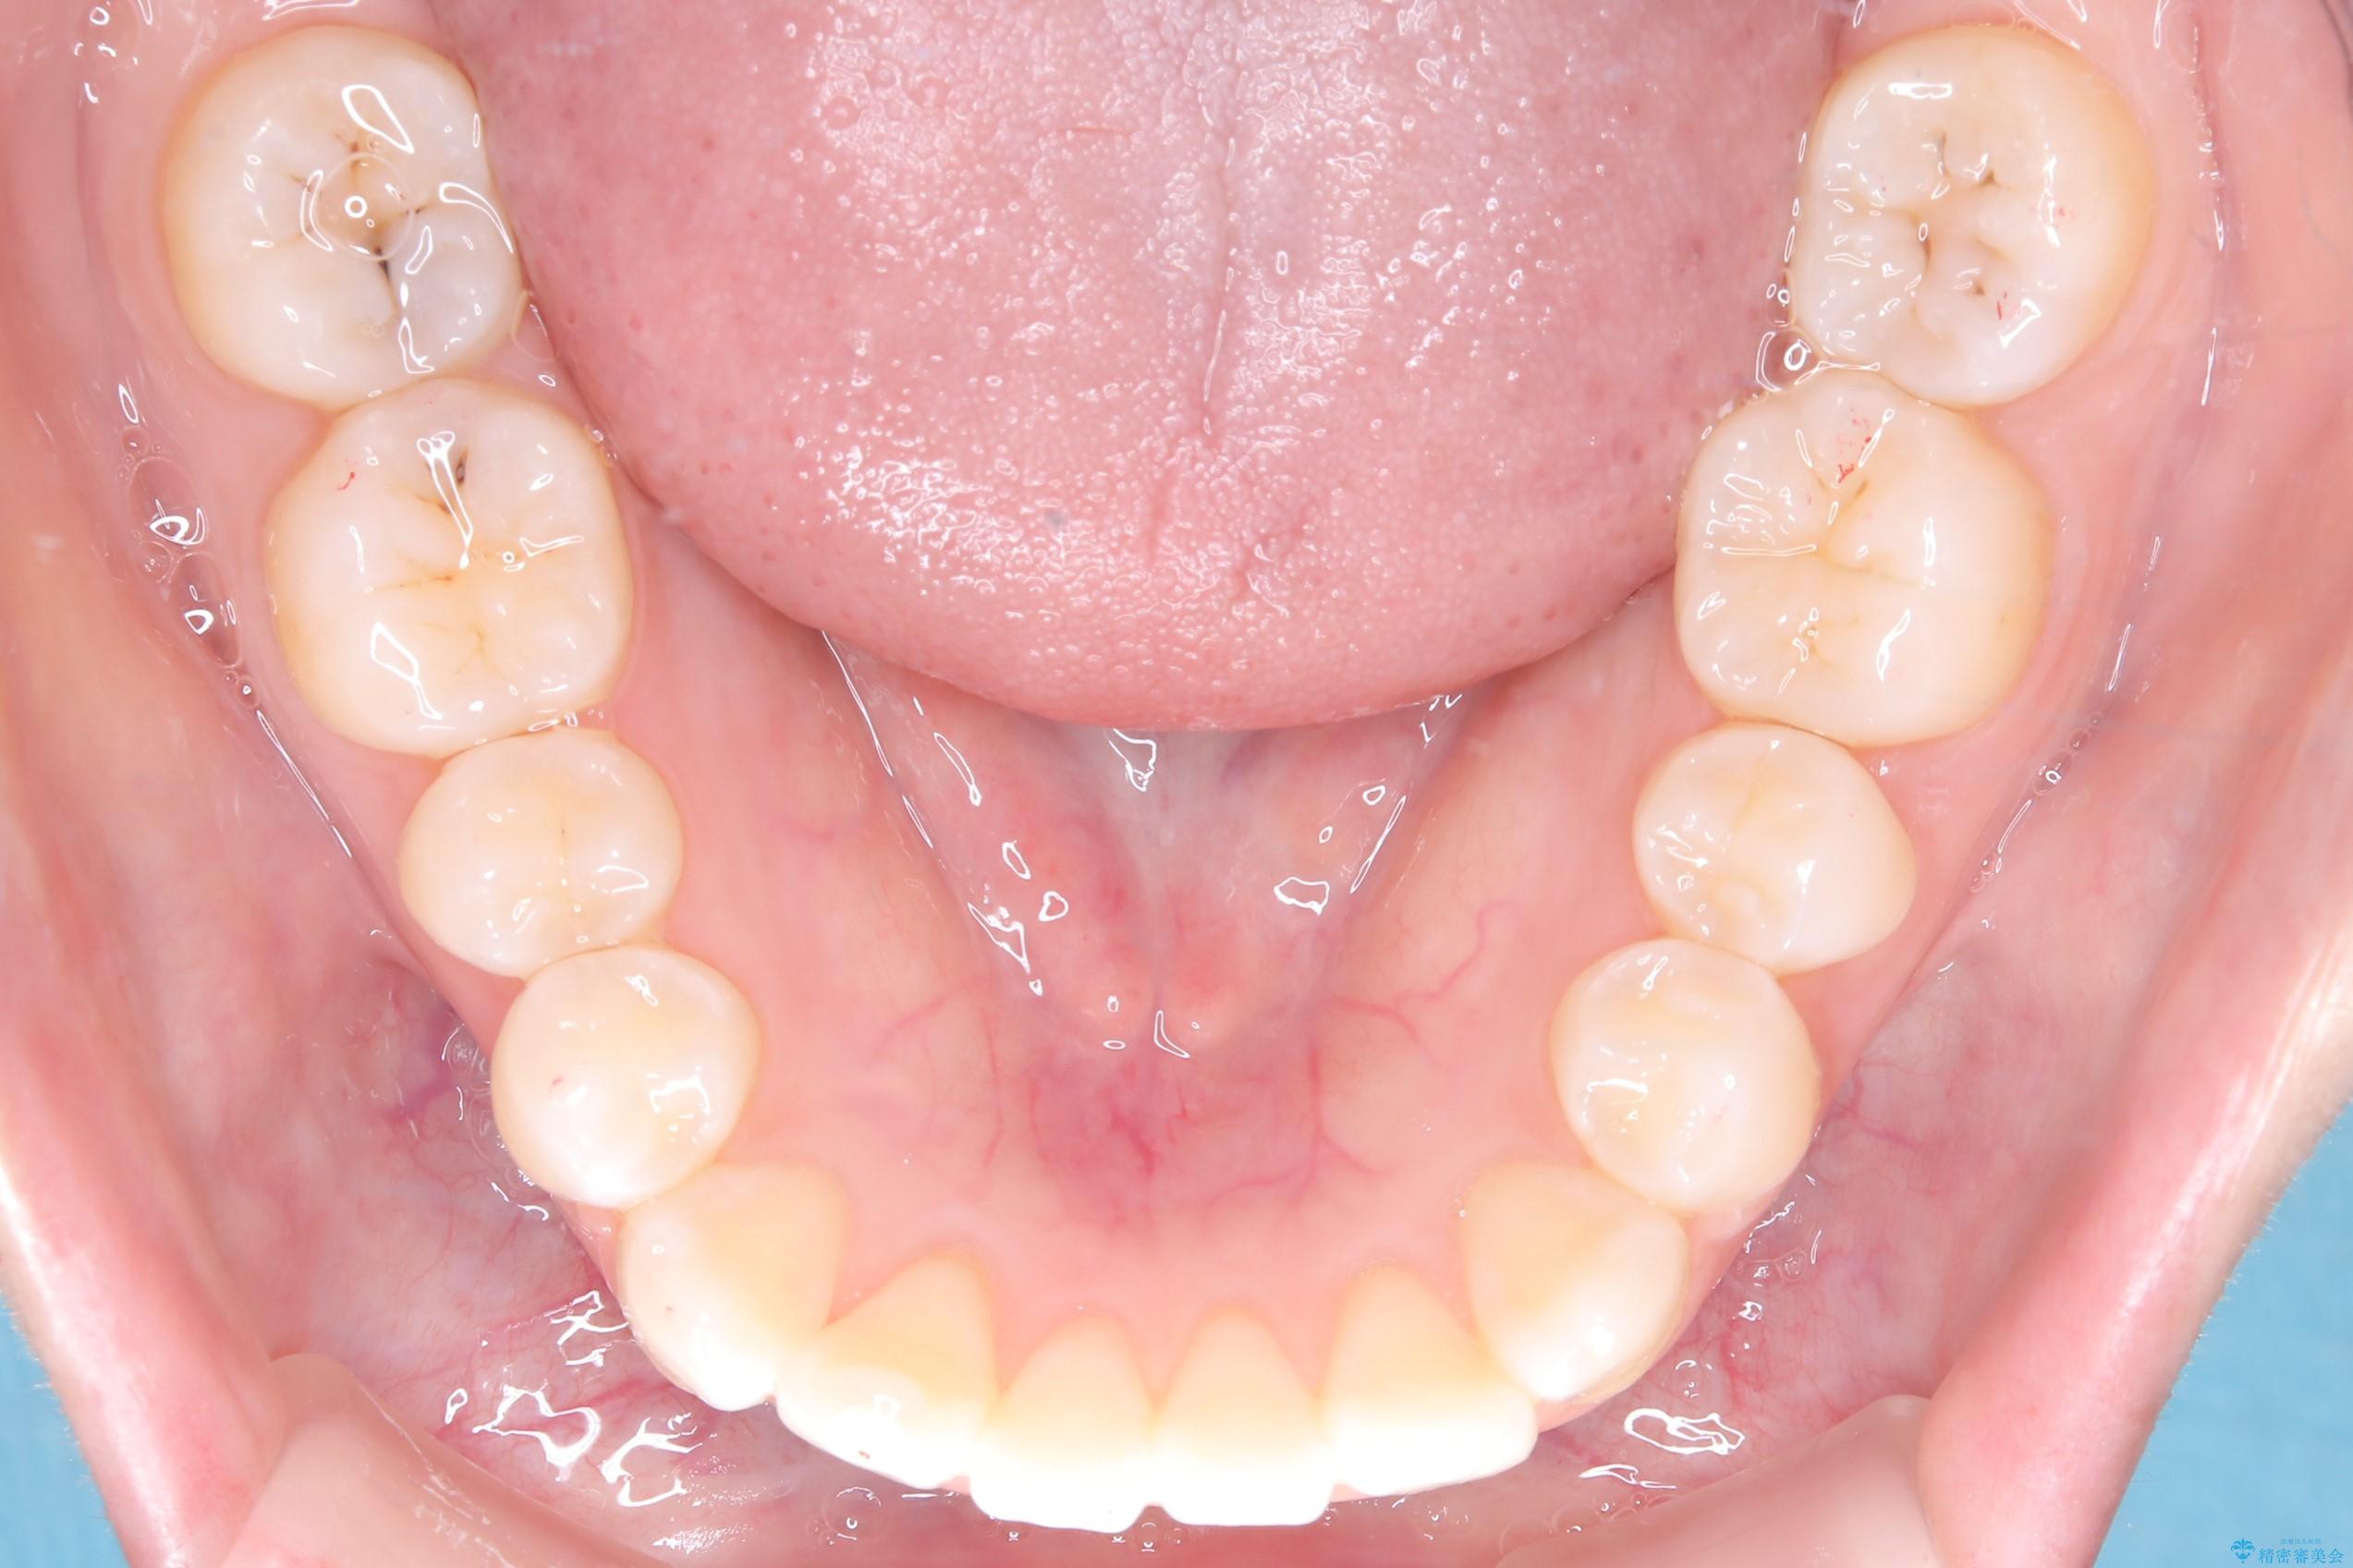

- 前歯のデコボコ(叢生)を気にされてご来院されました。精密な検査の結果、歯が並ぶスペースが不足していることが判明。患者様のご希望から、透明で目立ちにくいインビザライン(マウスピース矯正)による治療計画を立案しました。抜歯を避け、奥歯全体を奥へ動かす遠心移動という方法でスペースを確保し、前歯の叢生を解消することを目指します。

今回の矯正治療では、透明なマウスピース型の装置インビザラインを使用しました。この装置は取り外し可能で、日常生活で目立ちません。治療は、緻密に計算された計画に基づき、段階的に作製されたマウスピースを交換していくことで、奥歯から順に全体を後方へ移動させる遠心移動を実施。これにより、前歯を並べるための十分なスペースが確保され、デコボコが解消されました。抜歯することなく、機能的にも審美的にも整った美しい歯並びを獲得していただけました。